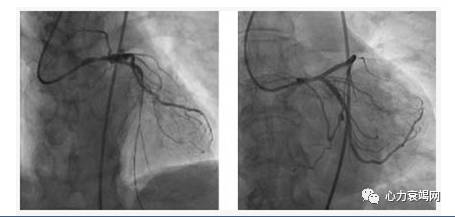

◆75岁男性,诊断:不稳定型心绞痛,冠心病三支病变(CTO),慢性左心衰(EF 23%),心功能Ⅳ级,2型糖尿病,高血压

◆实验室检查: 脑利钠肽前体:3781Pg/mL,高敏肌钙蛋白T 34.24pg/Ml

PCI前,在局麻下建立左侧股动静脉VA-ECMO,股动脉插管16Fr,股静脉插管20Fr,使用成人ECMO套包,流量2L/min

◆对于高风险PCI,预测心源性休克或心跳骤停可能发生(量化指征?),预先建立ECMO

◆严密监测植入ECMO的肢体远端血运

◆加强术后抗生素使用,预防感染

◆PCI成功后,血流动力学稳定情况下尽快撤除ECMO,避免长时间体外转流的一系列并发症

[1]Catheterization and cardiovascular intervention 2015